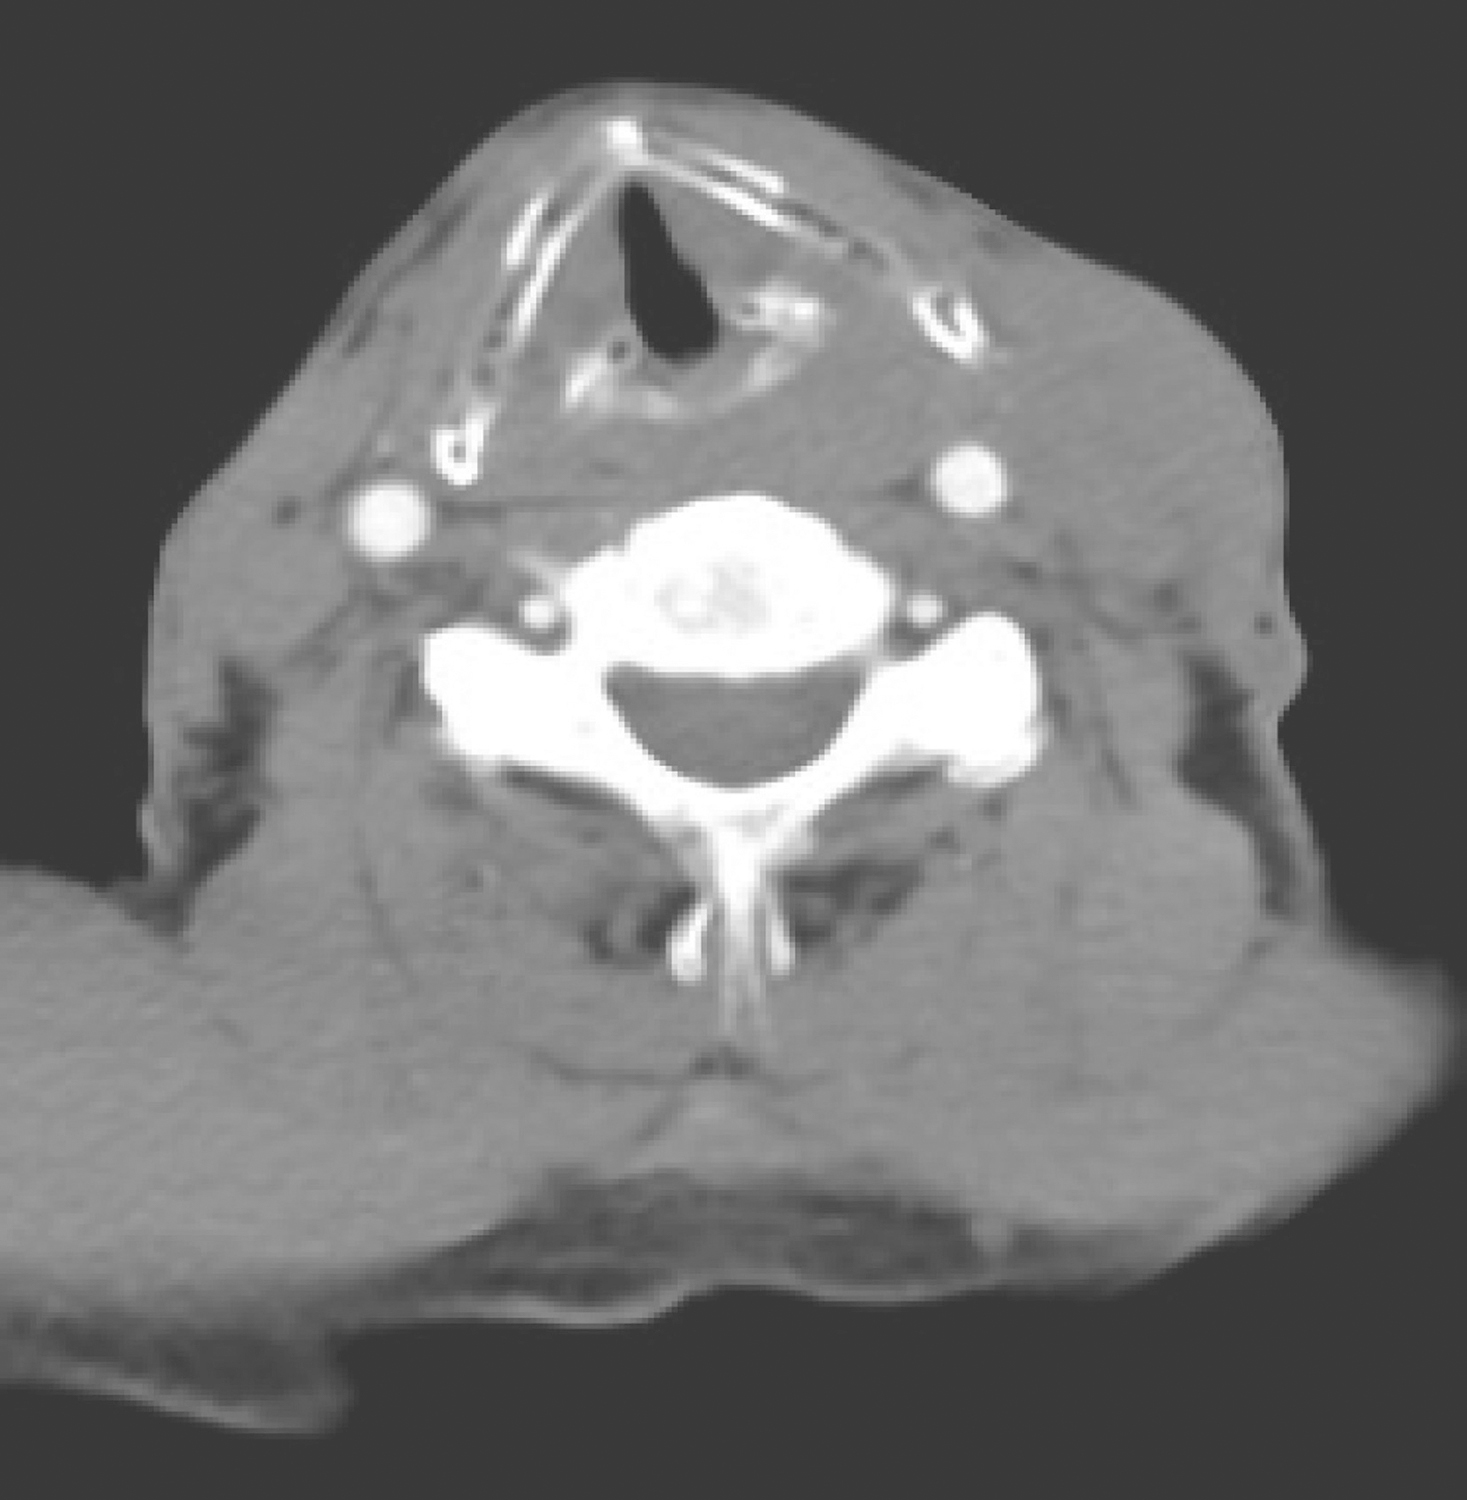

双侧杓会厌皱襞、环后可见软组织密度肿物,累及颈段食管(图1),增强扫描呈轻度不均质强化,左侧颈部胸锁乳突肌内侧肿大淋巴结影,密度欠均匀,边界不清,大者约3cm×2.5cm,增强扫描呈轻度强化(图2)。

图2颈胸部增强CT示左侧颈部胸锁乳突肌内侧肿大淋巴结影